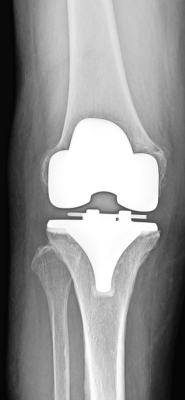

人工膝全置換術術後

当科で行っている主な手術は、骨折全般、変形性膝関節症に対する人工膝関節置換術(全置換、単顆置換)や高位脛骨骨切り術、膝半月板損傷に対する関節鏡手術、変形性股関節症に対する人工股関節置換術、神経・腱・血管に対する微小外科を含む手外科手術、肩腱板断裂に対する修復術、変形性肩関節症に対するリバース型人工肩関節置換術などです。

なお、人工膝関節置換術においては、症例に応じてナビゲーションの使用やオーダーメイド人工膝関節(PSI=Patient Specific Instrument)を用いた手術を行っております。また、人工股関節置換術においては、筋肉や腱の損傷を最小限にする低侵襲アプローチによる手術を行っております。